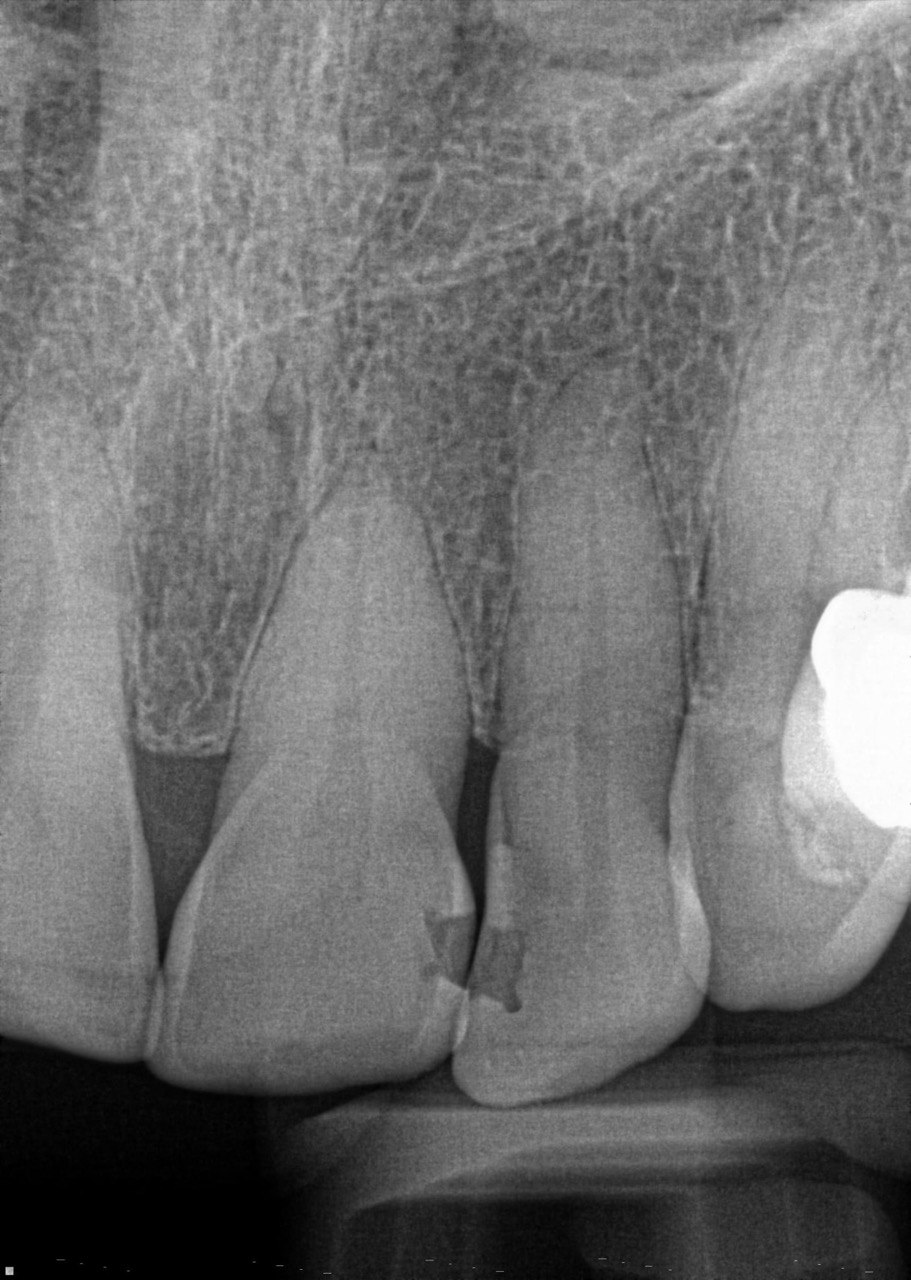

Question 7: What are the options associated with the distal surface of the tooth # 2.1 and mesial surface of the tooth # 2.2 respectively?

Question 8: What is the condition associated with the occlusal surface of the tooth # 1.6?